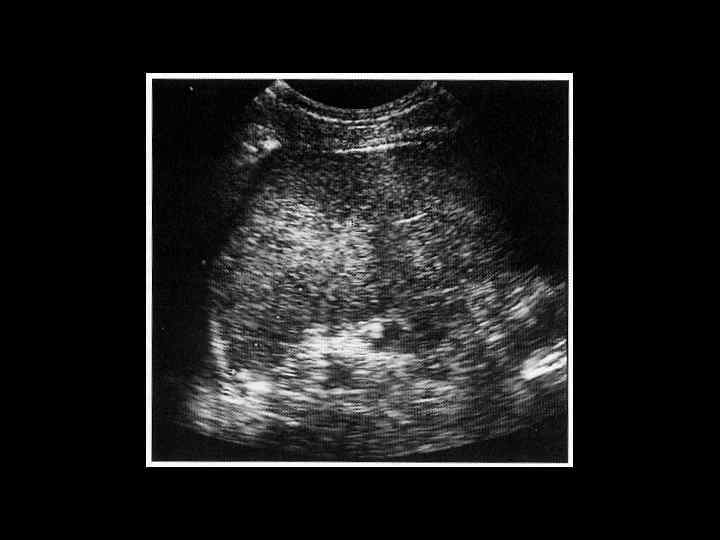

АКТУАЛЬНЫЕ ВОПРОСЫ РЕНТГЕНОЛОГИИ ЛУЧЕВАЯ ДИАГНОСТИКА ЗАБОЛЕВАНИЙ СЕЛЕЗЕНКИ Методы лучевого исследования: 1. Обзорная рентгенография 2. Ультразвуковое исследование 3. Компьютерная рентгеновская томография 4. Магнитно-резонансная томография 5. Радионуклидное исследование

АКТУАЛЬНЫЕ ВОПРОСЫ РЕНТГЕНОЛОГИИ ЛУЧЕВАЯ ДИАГНОСТИКА ЗАБОЛЕВАНИЙ СЕЛЕЗЕНКИ Кисты и абсцессы селезенки